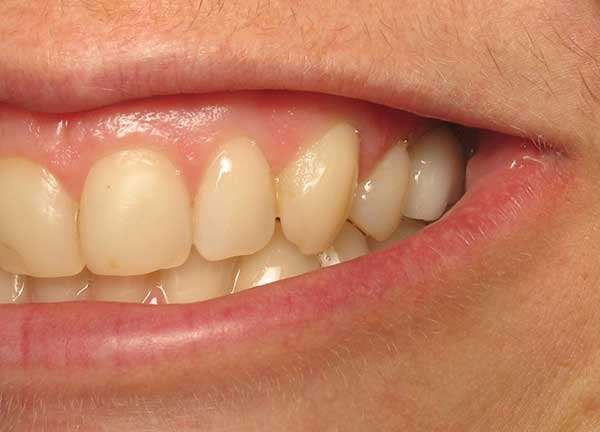

Corey E.

This patient had lost his front tooth due to an accident and had an Implant placed to replace it.